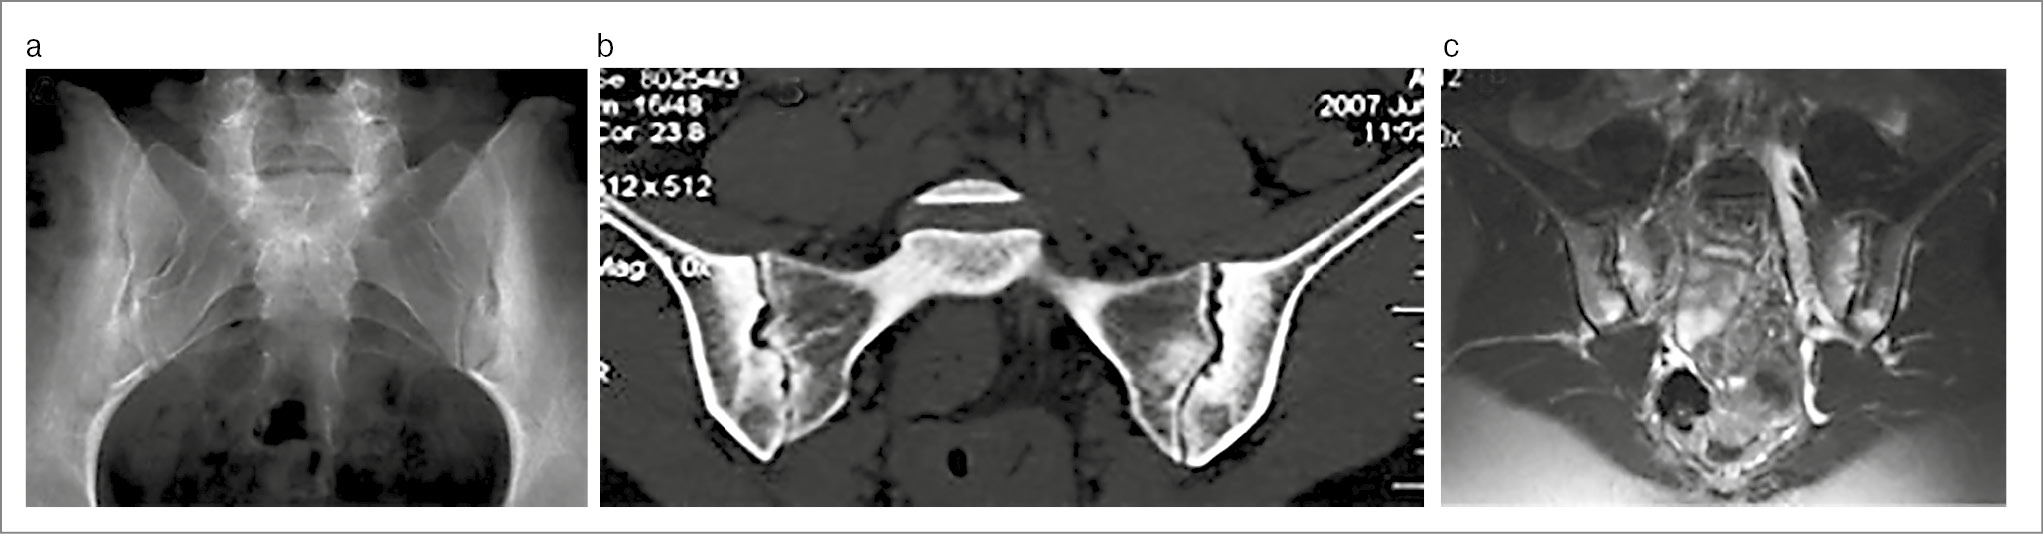

Пациентка В. 29 лет направлена на консультацию в 2023 г. с подозрением на АС. Жалобы на боли в нижней части спины и ягодиц, которые впервые остро возникли на 9-м месяце беременности (за 4 года до настоящей консультации), были стойкими и очень интенсивными. По результатам МРТ (рис. 1) сделано заключение о наличии сакроилиита. После родов боли продолжались, но постепенно стали менее сильными и непостоянными. Скорость оседания эритроцитов и уровень СРБ не повышались. Обнаружен HLA-B27. Установлен диагноз АС. Во время осмотра пациентки осанка существенно не нарушена, движения в позвоночном столбе не ограничены и безболезненны, болезненность при пальпации гребня левой подвздошной кости и в проекции левого КПС. Пересмотр МРТ четырехлетней давности позволил обнаружить стресс-переломы крестца с обеих сторон и массивный отек костного мозга вокруг линий переломов. Повторное МРТ-исследование (2023 г.) показало, что отек костного мозга в крестце отсутствует. На рентгеновском снимке признаков сакроилиита, нарушений целостности крестца не найдено. Рентгеноостеоденситометрия: показатели минеральной костной плотности в поясничном отделе позвоночника и проксимальном отделе бедренной кости в норме. Предположение об АС отвергнуто, установлен диагноз заживших (заживающих?) стресс-переломов крестца.

Рис. 1. Пациентка В. 29 лет. Стресс-переломы крестца, развившиеся на 9-м мес беременности. МРТ (коронарная проекция, режим STIR): в обеих боковых массах крестца отмечаются обширные зоны сигнала повышенной интенсивности (отек костного мозга), на фоне которого прослеживаются линии переломов (указаны стрелками).